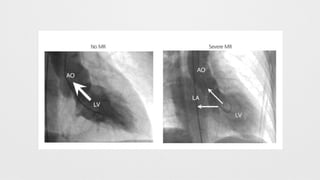

• The mitral regurgitation severity is based on the amount of contrast

regurgitate from the left ventricle into the left atrium via an

incompetent mitral valve and the opacification of the left atrium

used as a guide.

• Grade 1+ (mild) - Regurgitation essentially clears with each beat and

never opacifies the entire left atrium.

• Grade 2+ (moderate) - Regurgitation does not clear with one beat

and opacifies the entire left atrium after several beats.

• Grade 3+ (moderately severe) - The left atrium is opacified

completely and achieves equal opacification to the left ventricle.

• Grade 4+ (severe) - The entire left atrium is opacified within one beat

and becomes denser with each beat, with associated refluxing into

the pulmonary veins during systole.